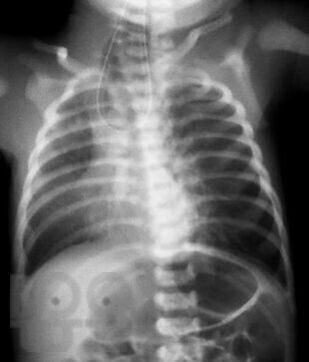

Диагностика и лечение хирургических заболеваний новорождённых и детей грудного возраста

В пособии рассматриваются современные принципы диагностики и лечения хирургических заболеваний новорождённых и детей первого года жизни, возможных осложнений и исходов. Акцентируем внимание студентов на эмбриогенез, этиологию и патогенез, классификацию, клинические проявления и выбор методов лечения. Пособие содержит вопросы для самоконтроля и список литературы для дополнительного изучения.